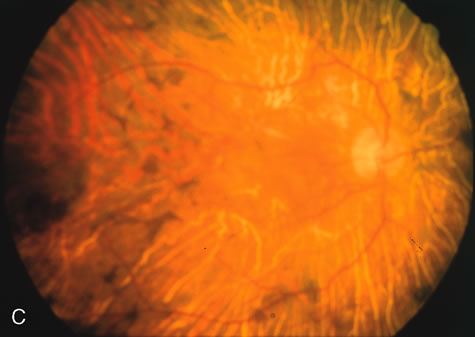

Fig. 1. Retinitis pigmentosa. A. A typical area of bone spicule pigmentation. B. Diffuse dye leakage is apparent throughout the posterior pole. C. The early angiogram shows dilated and irregular retinal radial peripapillary capillaries and perifoveal retinal capillaries. D. Leakage from these vessels are evident in the late angiogram.

Of more clinical importance is the role of FA in the diagnosis and treatment of cystoid macular edema (CME) (Fig. 1C and D). Stereoscopic FA indicates that the leakage, which may be diffuse or have the typical petaloid stellate appearance of CME, can come from the perifoveal retinal capillaries, from the choroid through the RPE, or from a combination of both sources.4 With the recent suggestion that CME in RP may be successfully treated with acetazolamide,5, 6 FA is thus important to document the diagnosis of CME, establish the origin(s) of leakage, and follow patients during and after therapy.